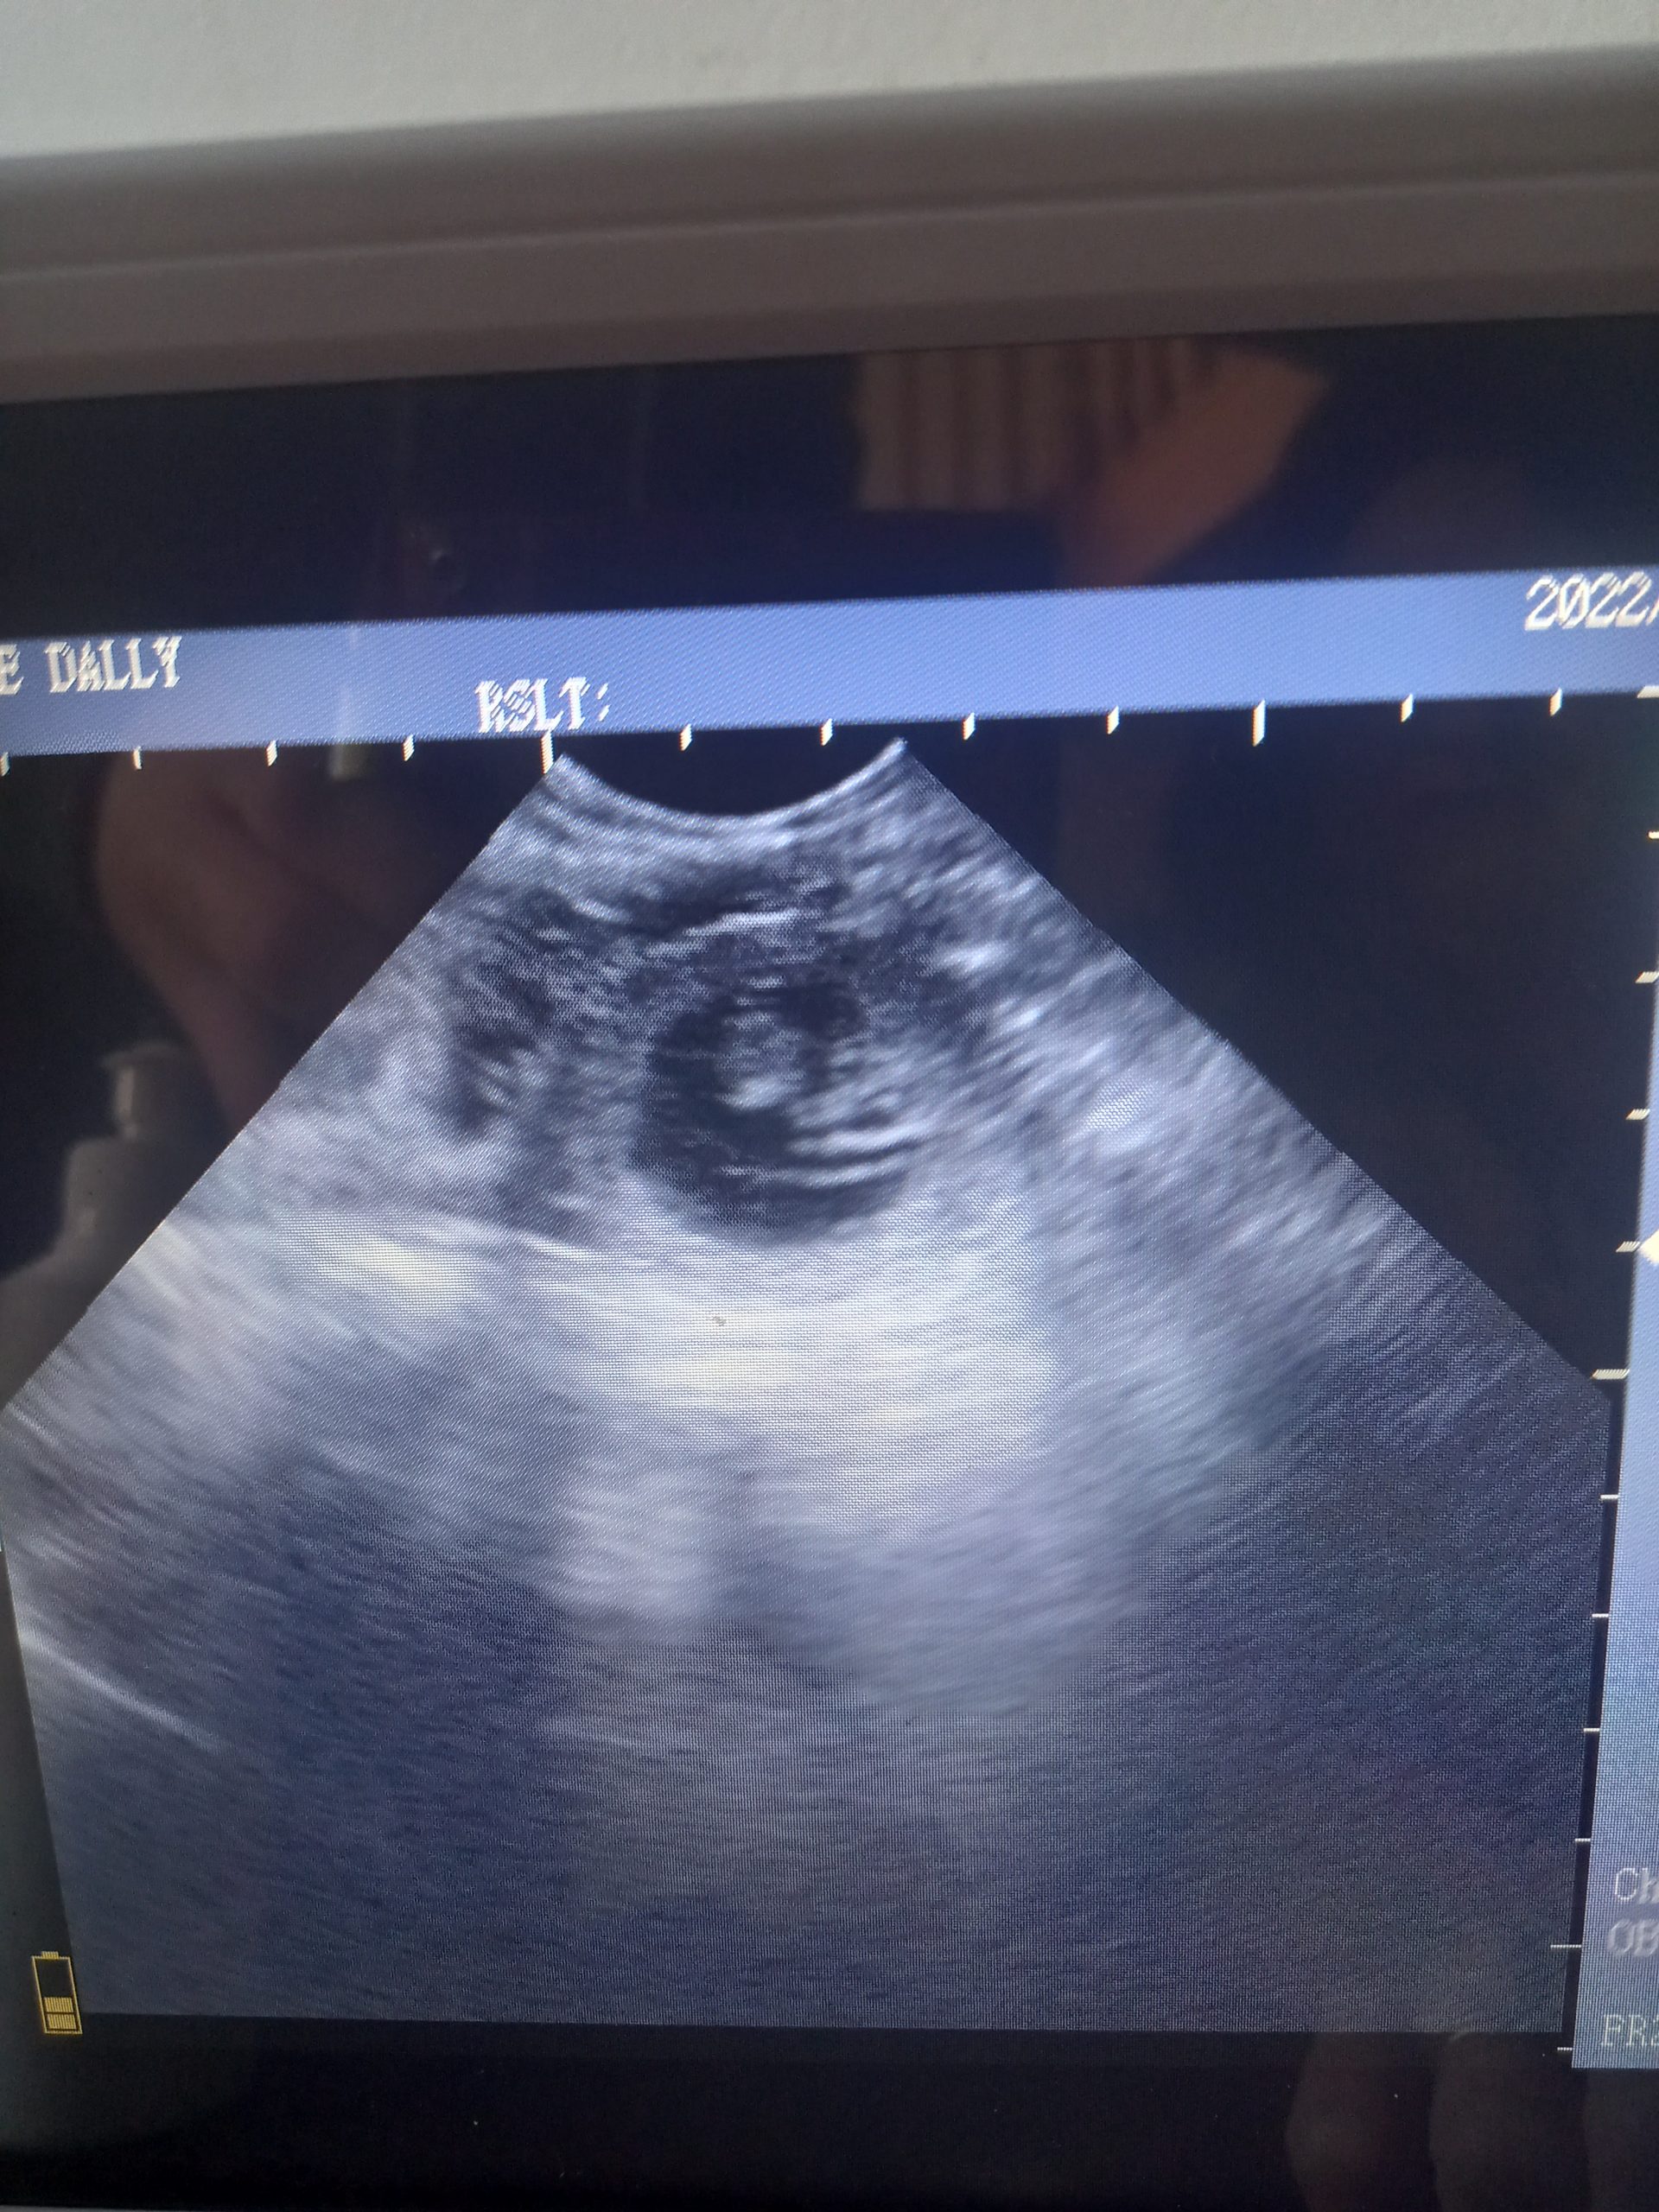

Beautiful scan of a 4yr old Labrador, confirmed multiple pups at 30days.